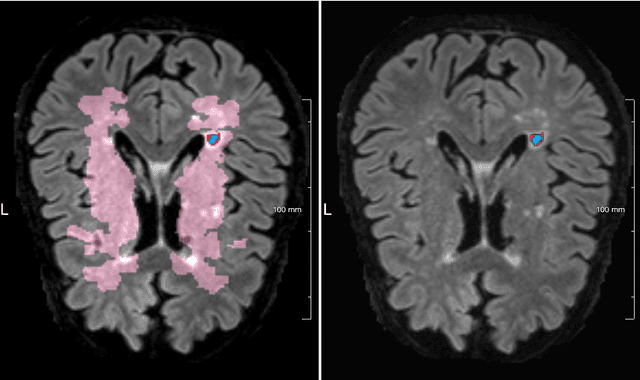

Lacunes of presumed vascular origin are fluid-filled cavities of between 3 - 15 mm in diameter, visible on T1 and FLAIR brain MRI. Quantification of lacunes relies on manual annotation or semi-automatic / interactive approaches; and almost no automatic methods exist for this task. In this work, we present a two-stage approach to segment lacunes of presumed vascular origin: (1) detection with Mask R-CNN followed by (2) segmentation with a U-Net CNN. Data originates from Task 3 of the "Where is VALDO?" challenge and consists of 40 training subjects. We report the mean DICE on the training set of 0.83 and on the validation set of 0.84. Source code is available at: https://github.com/hjkuijf/MixLacune . The docker container hjkuijf/mixlacune can be pulled from https://hub.docker.com/r/hjkuijf/mixlacune .